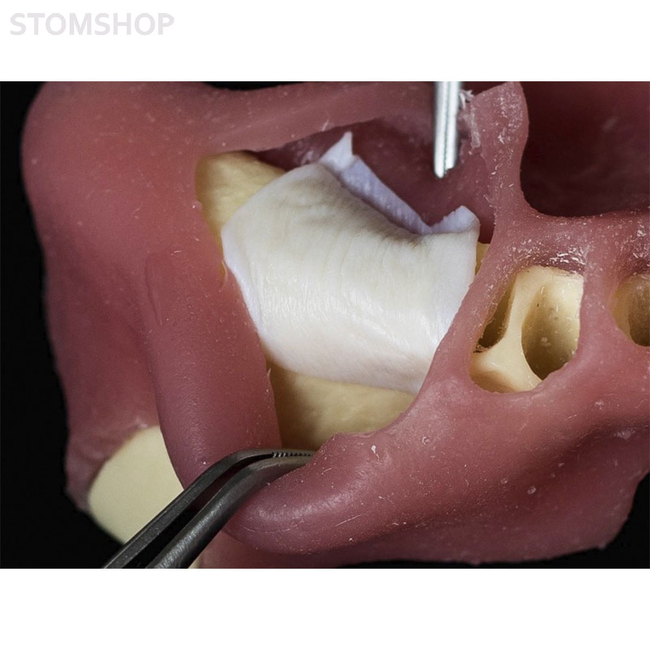

Еще более эластичная и гибкая. Адаптируется к любой форме дефекта, при этом прочная на разрыв. Легко фиксируется пинами и микровинтами. Мембрана cтабильно удерживает аугментат, обеспечивает оптимальные барьерные свойства даже при растяжении.

Состоит из коллагена I и III типа, имеет два слоя – серозный (гладкий) и фиброзный (ворсистый). При обнажении мембрана не инфицируется, ткани заживают вторичным натяжением. Предназначена для направленной костной регенерации (НКР) и направленной тканевой регенерации (НТР).

bioPLATE Membrane CONTUR применяется в следующих процедурах: